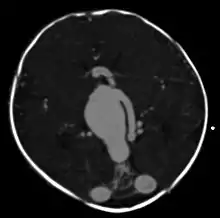

| Axial image from computerized tomography angiogram showing arteriovenous communication in vein of Galen malformation | |